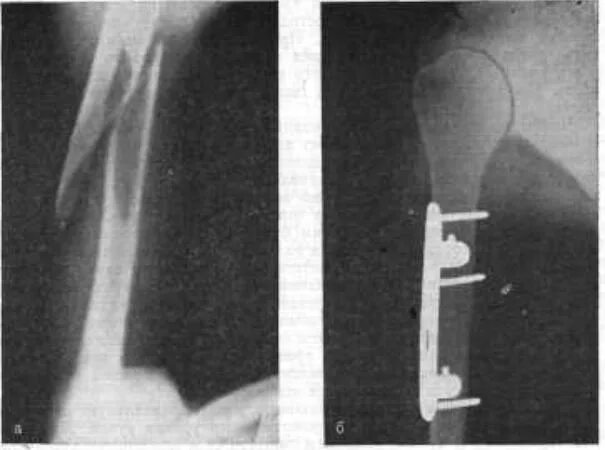

Оскольчатый перелом плеча со смещением